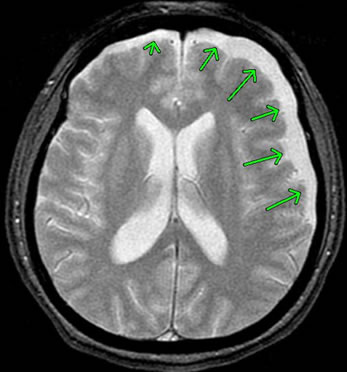

下記は、急性硬膜下血腫のMRI画像です。

画像の右側に、巨大な三日月型の白い部位が見られます。

この白い部分が「急性硬膜下血腫」です。